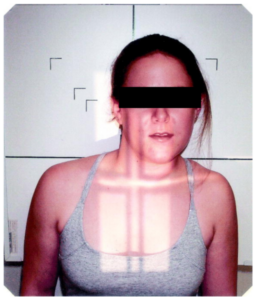

頭痛とめまいを引き起こした頭蓋頸椎の変位

6ヶ月前、約13kgの犬と散歩をしていて、突然頭痛とめまいが発生したとのことでした。

「この日はリードを腰に結んで出かけたのですが、無防備な状態で犬が急に引っ張ったため、体に衝撃がありました」